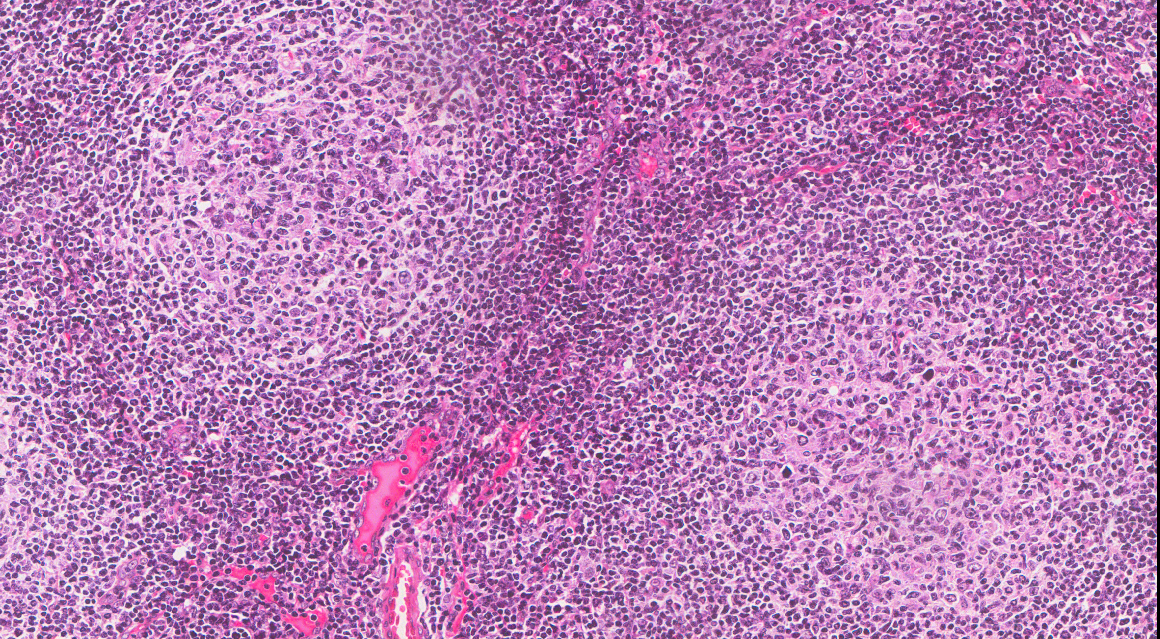

It is increasingly evident that the neoplastic cells in FL (illustrated as the follicular structures in the cover image) depend on stromal signals to grow, including the signaling performed by cytokines. A normal balance of cytokines is important to regulate physiological immune responses. These molecules allow the shifting between immune networks, such as Th1, Th2, and Th17, depending on the environmental stimulus. It is already known that there is a disruption of the cytokine balance in FL patients, as the serum profiles of these molecules in patients are different than the ones of healthy persons1. However, little is known about the genetic regulation of these molecules and its role in lymphomagenesis.